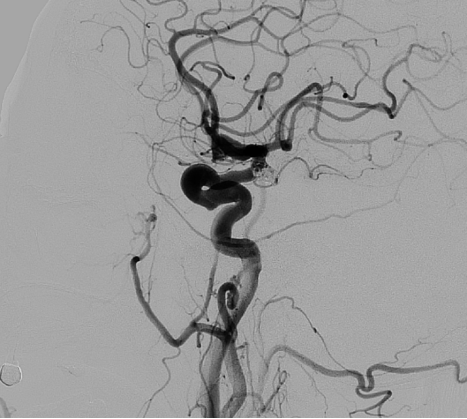

术后造影

术后造影结果(图6)显示动脉瘤填塞结果满意,载瘤动脉通畅,手术取得圆满成功。

图6 术后造影

本例患者为颈内动脉后交通段破裂动脉瘤,形态不规则且带子囊,其偏转方向及载瘤动脉近端弯曲增加了微导管精准到位和栓塞稳定性的挑战难度。手术采用AI导管塑形机器人完成自动化微导管塑形,使微导管实现一次性精准到位,且过程中无需微导丝辅助,显著降低了操作风险。术中,微导管头端始终保持稳定支撑,确保了填塞过程的顺利进行,最终手术效果理想。本案例展现了人工智能技术在动脉瘤破裂这一急诊场景下的高效应用与实践,在未来,该技术将为更多患者提供更加安全、高效的治疗选择。